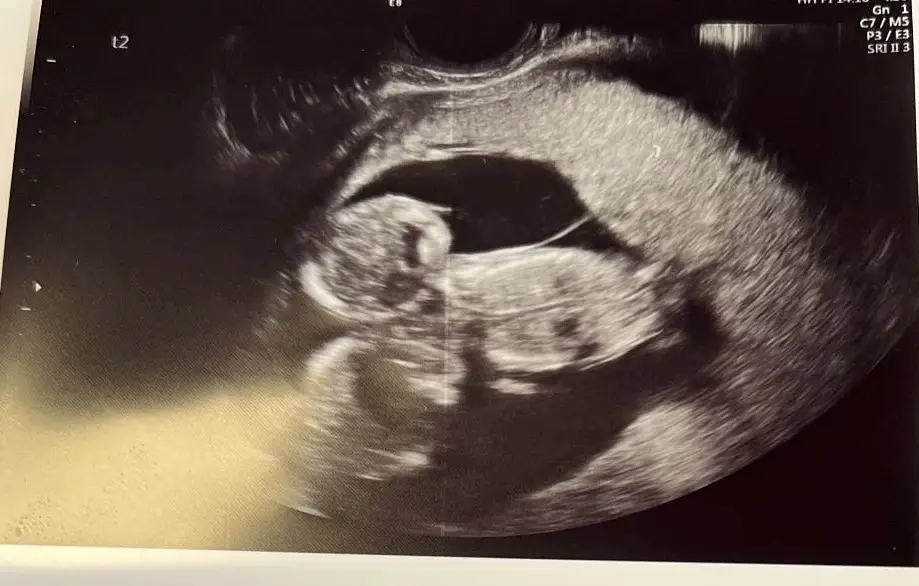

New parents Jake Hammerton, 22, and his partner Caitlin Knight, 20, were thrilled to discover that Caitlin was pregnant. At their 22-week scan, the couple from Sheffield found out that they were having identical triplet boys – a one in 200 million case without IVF – so naturally they went away and started prepping for the arrival of their little lads.